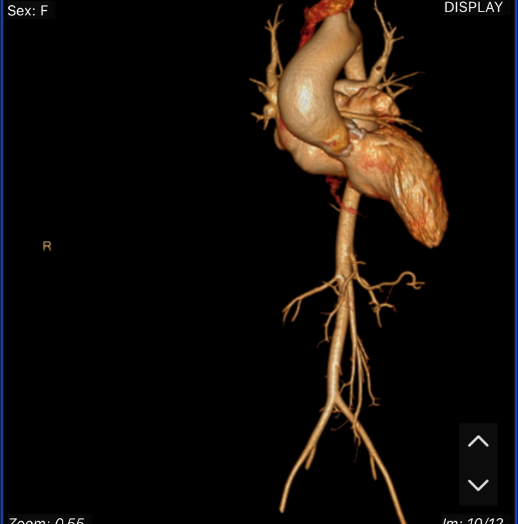

近日,哈尔滨医科大学附属第一医院谢宝栋、康凯、薛阳红教授团队,应用ScienCrown瓣膜成功完成一例急诊TAVR手术。该患者因“胸闷气短4月余”入院,入院心衰严重,考虑患者年轻,初始治疗方案为药物调理后行外科主动脉瓣置换术。然而,经多次药物调整后,患者一般状况及心功能仍呈进行性恶化,心力衰竭症状显著加重,血压60/40mmHg左右,多脏器功能损伤,体质虚弱。面对紧急病情,团队经全面评估后,考虑患者无法耐受外科开胸处理,果断调整治疗策略,为患者制定了急诊TAVR手术方案。术后即刻,患者主动脉瓣狭窄得到解除,血流动力学迅速趋于稳定,临床症状明显缓解,最终成功挽救了患者生命。本例手术的成功,彰显了术者团队在面对急危重症时卓越的应急决策与手术能力。

基于患者病情危重、一般状况与心功能进行性恶化,且无法耐受传统外科手术,团队决定施行急诊经导管主动脉瓣置换术(TAVR)。鉴于情况紧急,无法完成常规的术前CT精细评估,术者团队果断决策,采用快速CT测量结合术中超声心动图及主动脉根部造影等多模态影像技术,进行综合研判,并据此制定了周密的球囊扩张与瓣膜植入策略。

近年来,临床实践不断证实,急诊经导管主动脉瓣置换术(TAVR)已成为治疗因严重主动脉瓣狭窄(AS)导致急性失代偿或心源性休克患者的可行且有效的策略,能显著降低患者死亡率并改善预后。与择期TAVR相比,急诊TAVR常因患者病情危重而缺乏充分的术前影像学评估,手术难度与风险显著增高,对多学科团队的整体诊疗能力与应急水平提出了更高要求。本例患者入院后一般状况急速恶化,左心室射血分数(LVEF)低至26%,心功能处于极差状态,符合急诊TAVR手术指征。术中,在缺乏术前CT影像进行精确解剖评估与方案规划的情况下,操作复杂性进一步增加,高度依赖术者团队的即时判断、娴熟技术及丰富的紧急情况处理经验。